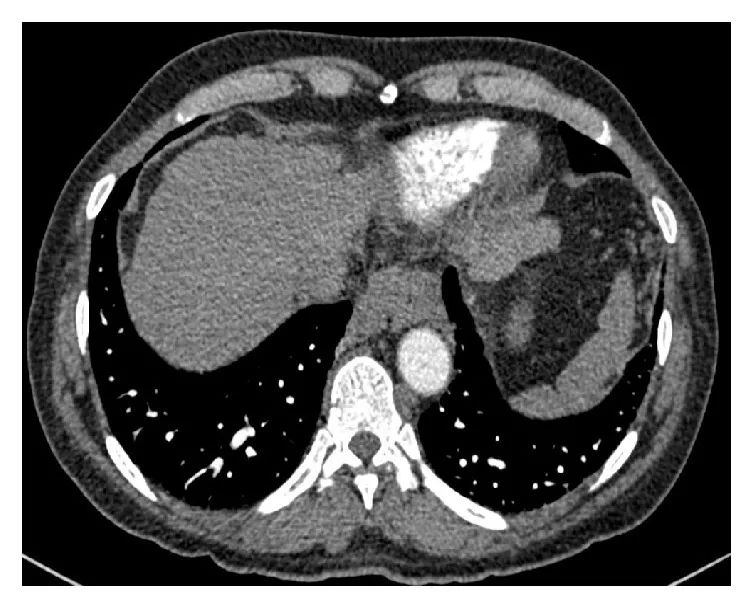

肺功能检测提示第1秒用力呼气容积(FEV1)和用力肺活量(FVC)降低,但FEV1/FVC正常。胸部CT显示双侧基底肺动脉扩张明显和肝脏边缘不规则,但没有肺气肿或纤维化改变。

图3 胸部CT显示明显的肺血管和不规则的肝脏边缘